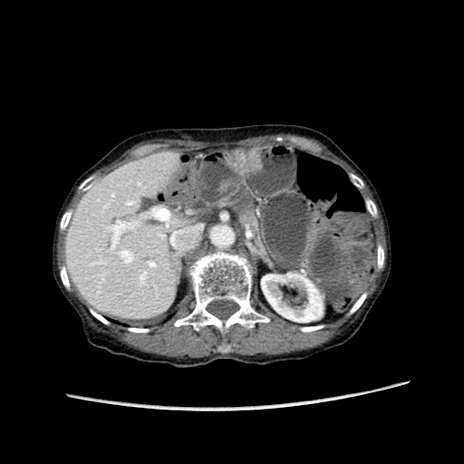

症例25(横断像)

【症例】80歳代女性

【主訴】胸のつかえ感

【現病歴】約9時間前に食後から胸のつかえた感じあり、嘔吐あり、来院。

【既往歴】胃癌(全摘)、胆摘、虫垂炎

【身体所見】心窩部に圧痛あり、反跳痛なし。

【データ】WBC 5700、CRP 0.05